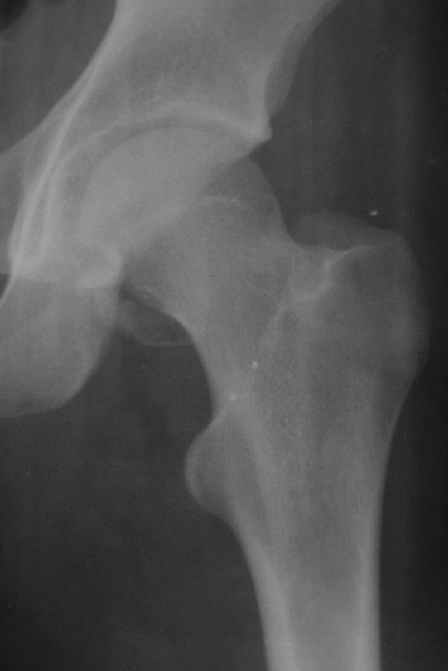

Уважаемые коллеги! Заканчивая обследование больного с переломо-вывихом бедра сделал ему обычные R-томограммы. Кажется удалось "поймать" и отломок и донорское место. Мои выводы - в скиаграмме. Считаю, что это передне-нижний фрагмент головки, образовавшийся вследствии отрывного перелома. На томограммах отломок обозначаю длинной стрелкой, а место откуда он оторвался - более короткой. Учитывая тот факт, что его размеры по КТ 25 х 15 мм считаю, что его фиксация на место необходима для профилактики артроза, что при 16-ти летнем возрасте пациента важно в плане максимального отодвигания эндопротезирования. Планирую оперировать его 24.05.05 г. Результаты представлю.

Прямой при поступлении

Прямой 19.05

Несколько соображений к "картинкам". На прямом снимке и КТ-томограммах все типичные линии вертлужной впадины: крыша, передняя стенка, задняя стенка - сохранены. На КТ-сканах 6 и 7 появляется фрагментация головки. С учетом R-томограмм отломок расположен спереди-снизу, а не сзади-сверху от сустава, как написано в описании КТ.